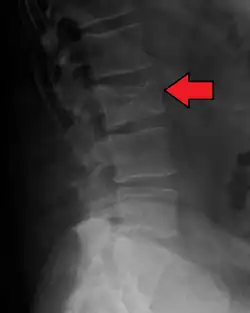

Medical imaging

The diagnostic examination of a person with suspected multiple myeloma typically includes a skeletal survey. This is a series of X-rays of the skull, axial skeleton, and proximal long bones. Myeloma activity sometimes appears as "lytic lesions" (with local disappearance of normal bone due to resorption) or as "punched-out lesions" on the skull X-ray ("raindrop skull"). Lesions may also be sclerotic, which is seen as radiodense.[76] Overall, the radiodensity of myeloma is between −30 and 120 Hounsfield units (HU).[77] Magnetic resonance imaging is more sensitive than simple X-rays in the detection of lytic lesions. An MRI may supersede a skeletal survey, especially when vertebral disease is suspected. Occasionally, a CT scan is performed to measure the size of soft-tissue plasmacytomas. Nuclear Medicine Bone scans are typically not of any additional value in the workup of people with myeloma (no new bone formation; lytic lesions not well visualized on nuclear bone scan).

-

X-ray of the forearm, with lytic lesions -

Skull X-ray showing multiple lucencies due to multiple myeloma -

Multiple myeloma in the upper arm -

Pathological fracture of the lumbar spine due to multiple myeloma -

A CT of the brain revealed a lytic lesion in the left temporal bone (right side of image), and petrous temporal bones involving the mastoid segment of the facial nerve canal. Red arrows: lesion; green arrow: normal contralateral facial nerve canal. The lesions are consistent with a myeloma deposit.